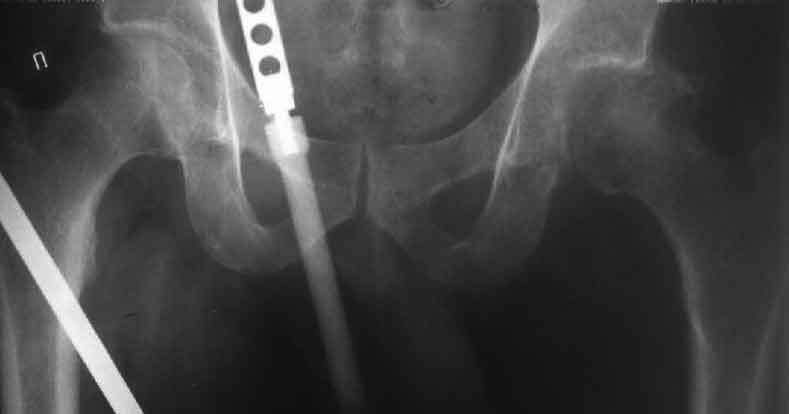

у нас, вероятно, первым этапом наложили бы аппарат таз-бедро без резекции головки, потом протезирование после восстановления длины.

> у нас, вероятно, первым этапом наложили бы аппарат таз-бедро без

> резекции головки, потом протезирование после восстановления длины.

Насчет 8 см согласен с А.Н. Челноковым, это наверное ортопедическое за счет приводящей, сгибательной контрактуры и, возможно, колена. на ликвидацию укорочения у нас обычно уходит около 2-х нед. снимки в приложении, возможно не очень показательные, но других с ходу не нашел, завтра еще поищу.

Метод беcкровного низведения, предложенный Max&Co, мне кажется более логичным, чем поэтапность с удалением головки и с дальнейшим скелетним вытяжением.

Протезировать можно одномоментно, но тогда потеряется эффект от дистракции на мобильном аппарате. На дистрагированных мягких тканях по

Илизарову "закон напряжения растяжения" (tension stress) лучше делать реконструктивные операции, чем на контрагированных, твердых, как камень мышцах.

Другое преимущество - больной, самостоятельно передвигаясь, не будет обузой для обслуживающего персонала и в течение первого этапа может

находиться дома. После достижения дистракции отпадет необходимость предлагаемого двойного доступа с кровотечением!!, которые послеоперационно имеют большую вероятность осложнений, например, вывих протеза из-за ослабления сустава со всех сторон.